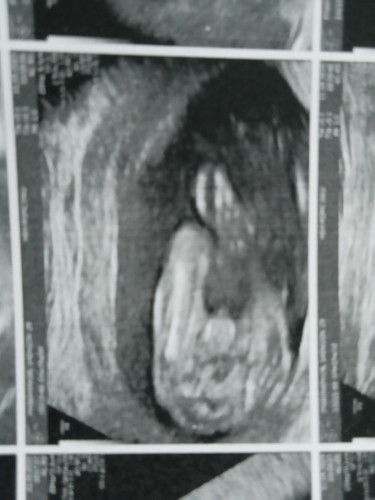

#19week #ทีมกุมภา67ค่ะ อยากมาอวดซาวเพศน้องชัดมาก คุณหมอก็ใจดีมากค่ะ ซาวให้นานมาก เสียแค่ค่ายา30บาท ตอนแรกแอบกลัวเคยได้ยินคนพูดกันว่าฝาก รพ รัฐ คุณหมอไม่ซาวให้ พี่พยาบาลแอบดุ แต่ รพ ที่ แม่ไปฝากนี้ ซาวให้เป็นชั่วโมงค่ะ กับอาจารย์หมอ และพี่ๆพยาบาลก็บริการดีมากๆๆๆ ☺️ แถมปริ้นรูปให้สามหน้ากระดาษ 🎉